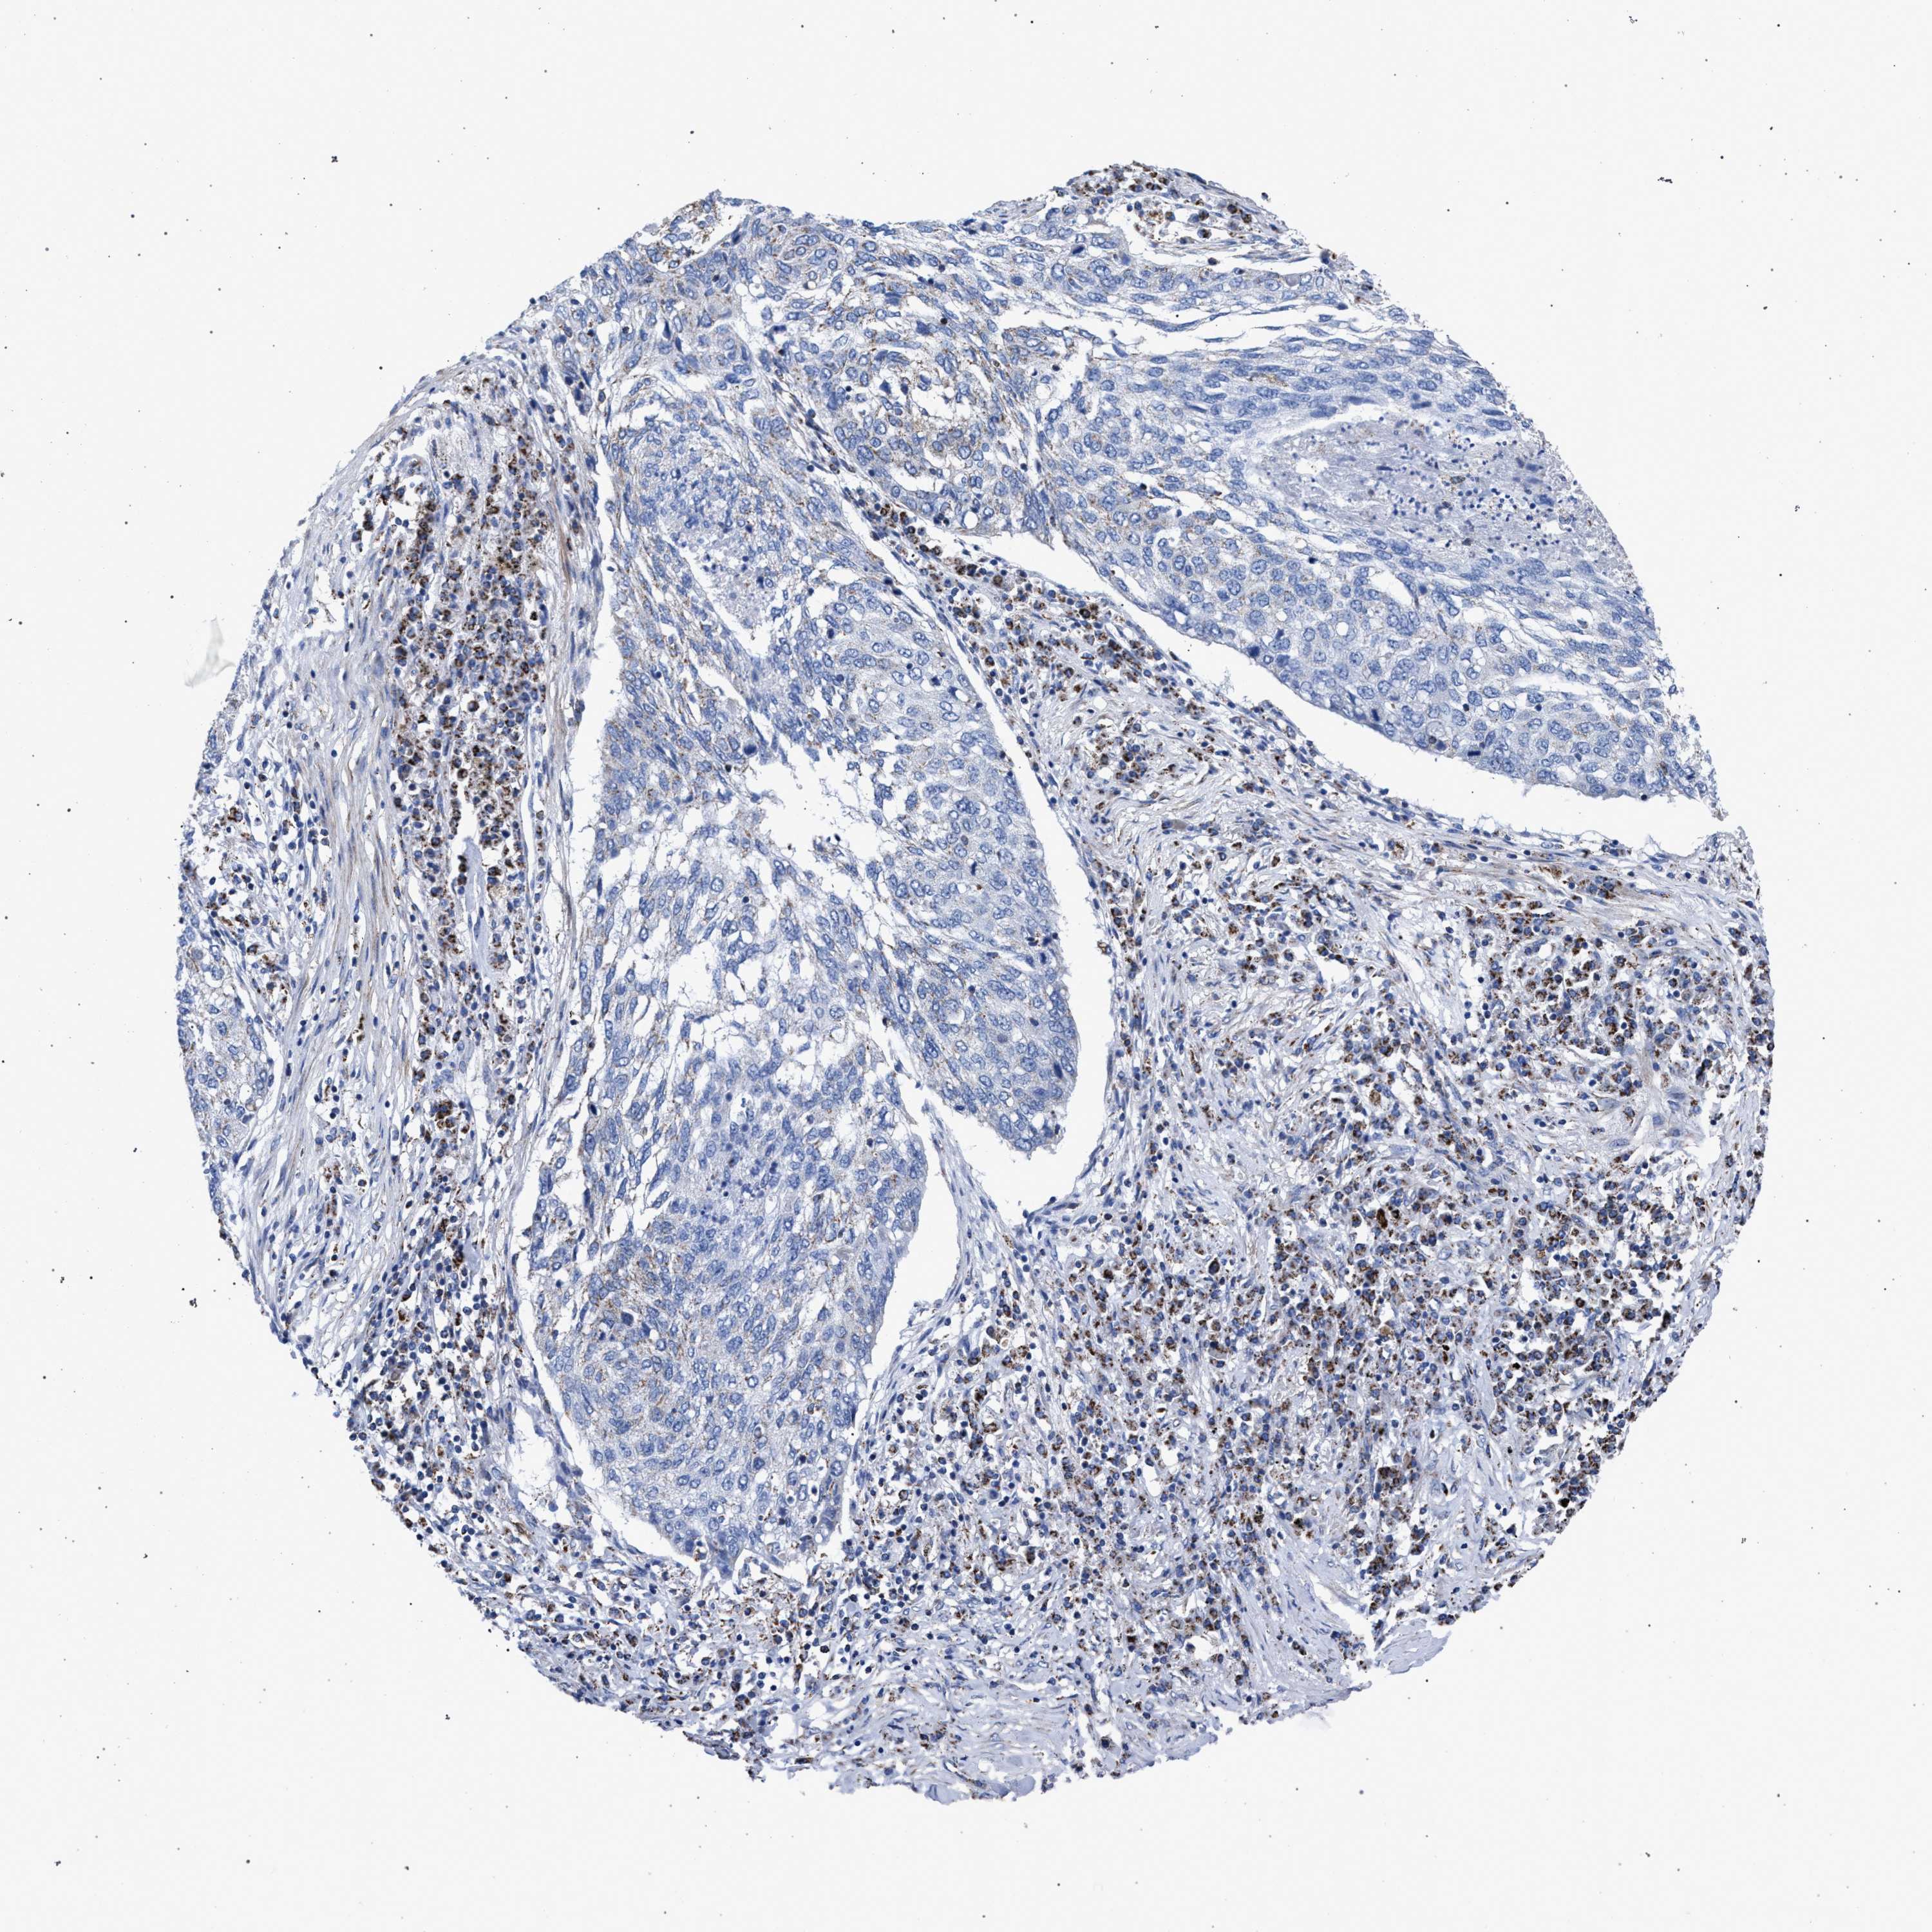

LUNG SQUAMOUS CELL CARCINOMA (TCGA) - Interactive survival scatter ploti

The Survival Scatter plot shows the clinical status (i.e. dead or alive) for all individuals in the patient cohort, based on the same data that underlies the corresponding Kaplan-Meier plots. Patients that are alive at last time for follow-up are shown in blue and patients who have died during the study are shown in red.

The x-axis shows the expression levels (FPKM) of the investigated gene in the tumor tissue at the time of diagnosis. The y-axis shows the follow-up time after diagnosis (years). Both axes are complimented with kernel density curves demonstrating the data density over the axes. The top density plot shows the expression levels (FPKM) distribution among dead (red) and alive patients (blue). The right density plot shows the data density of the survived years of dead patients with high and low expression levels respectively, stratified using the cutoff indicated by the vertical dashed line through the Survival Scatter plot. This cutoff is automatically defined based on the FPKM cutoff that minimizes the p-score. The cutoff can be changed by dragging the vertical line or by entering a cutoff value in the square labeled "Current cut-off".

Under the Survival Scatter plot the p-score landscape (black curve; left axis) is shown together with dead median separation (red curve; right axis). Dead median separation is the difference in median mRNA expression between patients who have died with high and low expression, respectively. It is calculated as follows: median FPKM expression of dead patients with high expression - median FPKM expression of dead patients with low expression. This is intended to aid the user in visually exploring custom cutoffs and the associated p-scores and dead median separation.

Individual patient data is displayed and can be filtered by clicking on one or more of the category buttons on the top of the page. Categories describing expression level and patient information include: high, low, alive, dead, female, male and tumor stages. The scale of the x-axis can be toggled between linear and log-scale by clicking on the "x log" button. Mouse-over function shows TCGA ID, patient information and mRNA expression (FPKM) for each patient.

& Survival analysisi

Kaplan-Meier plots summarize results from analysis of correlation between mRNA expression level and patient survival. Patients were divided based on level of expression into one of the two groups "low" (under cut off) or "high" (over cut off). X-axis shows time for survival (years) and y-axis shows the probability of survival, where 1.0 corresponds to 100 percent.

ACADS is not prognostic in Lung Squamous Cell Carcinoma (TCGA)

: 14.24